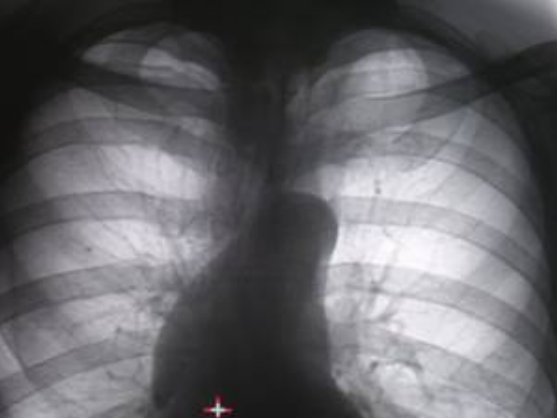

Протокол. На прямой цифровой флюорограмме органов грудной полости (1), произведенной в прямой стандартной проекции слева в 1 межреберье дифференцируется малоинтенсивная очаговоподобная тень. При цифровой обработке изображения (2) – эквилизация, увеличение в два раза, вышеописанная тень неправильной овальной формы, малой интенсивности с нечеткими контурами. На томограммах – оптимальный срез 11 см. (3, 4) на уровне 1 ребра определяется крупноочаговая тень размерами 1,0 х 0,8 см. средней интенсивности, почти однородной структуры с неровными, нечёткими контурами за счёт мелкой лучистости по контуру.

1. прямая цифровая флюорограмма органов грудной полости